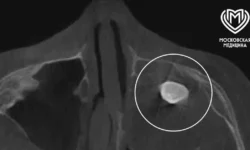

Пострадавший упал в погреб, где наткнулся на фрагмент металлической трубы длиной в четверть метра. Любопытно, что, несмотря на серьёзность ситуации, к медикам он обратился лишь спустя трое суток после инцидента.

Во время операции специалисты не только аккуратно извлекли предмет диаметром 2,5 см, но и устранили повреждение двенадцатиперстной кишки. Удивительно, что труба обошла важнейшие сосуды и органы, причинив минимальный ущерб! Уже через две недели пациент покинул медучреждение в отличном расположении духа и прекрасной физической форме.